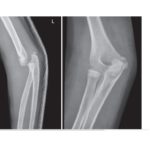

Distal Femur Physeal Fractures

Courtesy: Prof Nabil Ebraheim, University of Toledo, Ohio, USA Distal Femoral Physeal Fractures (Pediatric) Overview Injury to the distal femoral physis in children One of the most important pediatric knee injuries Clinical Importance High risk of growth arrest (~50–60%) Risk increases with: Displacement High-energy trauma Key Clinical Point In children presenting with: Suspected MCL/LCL […]